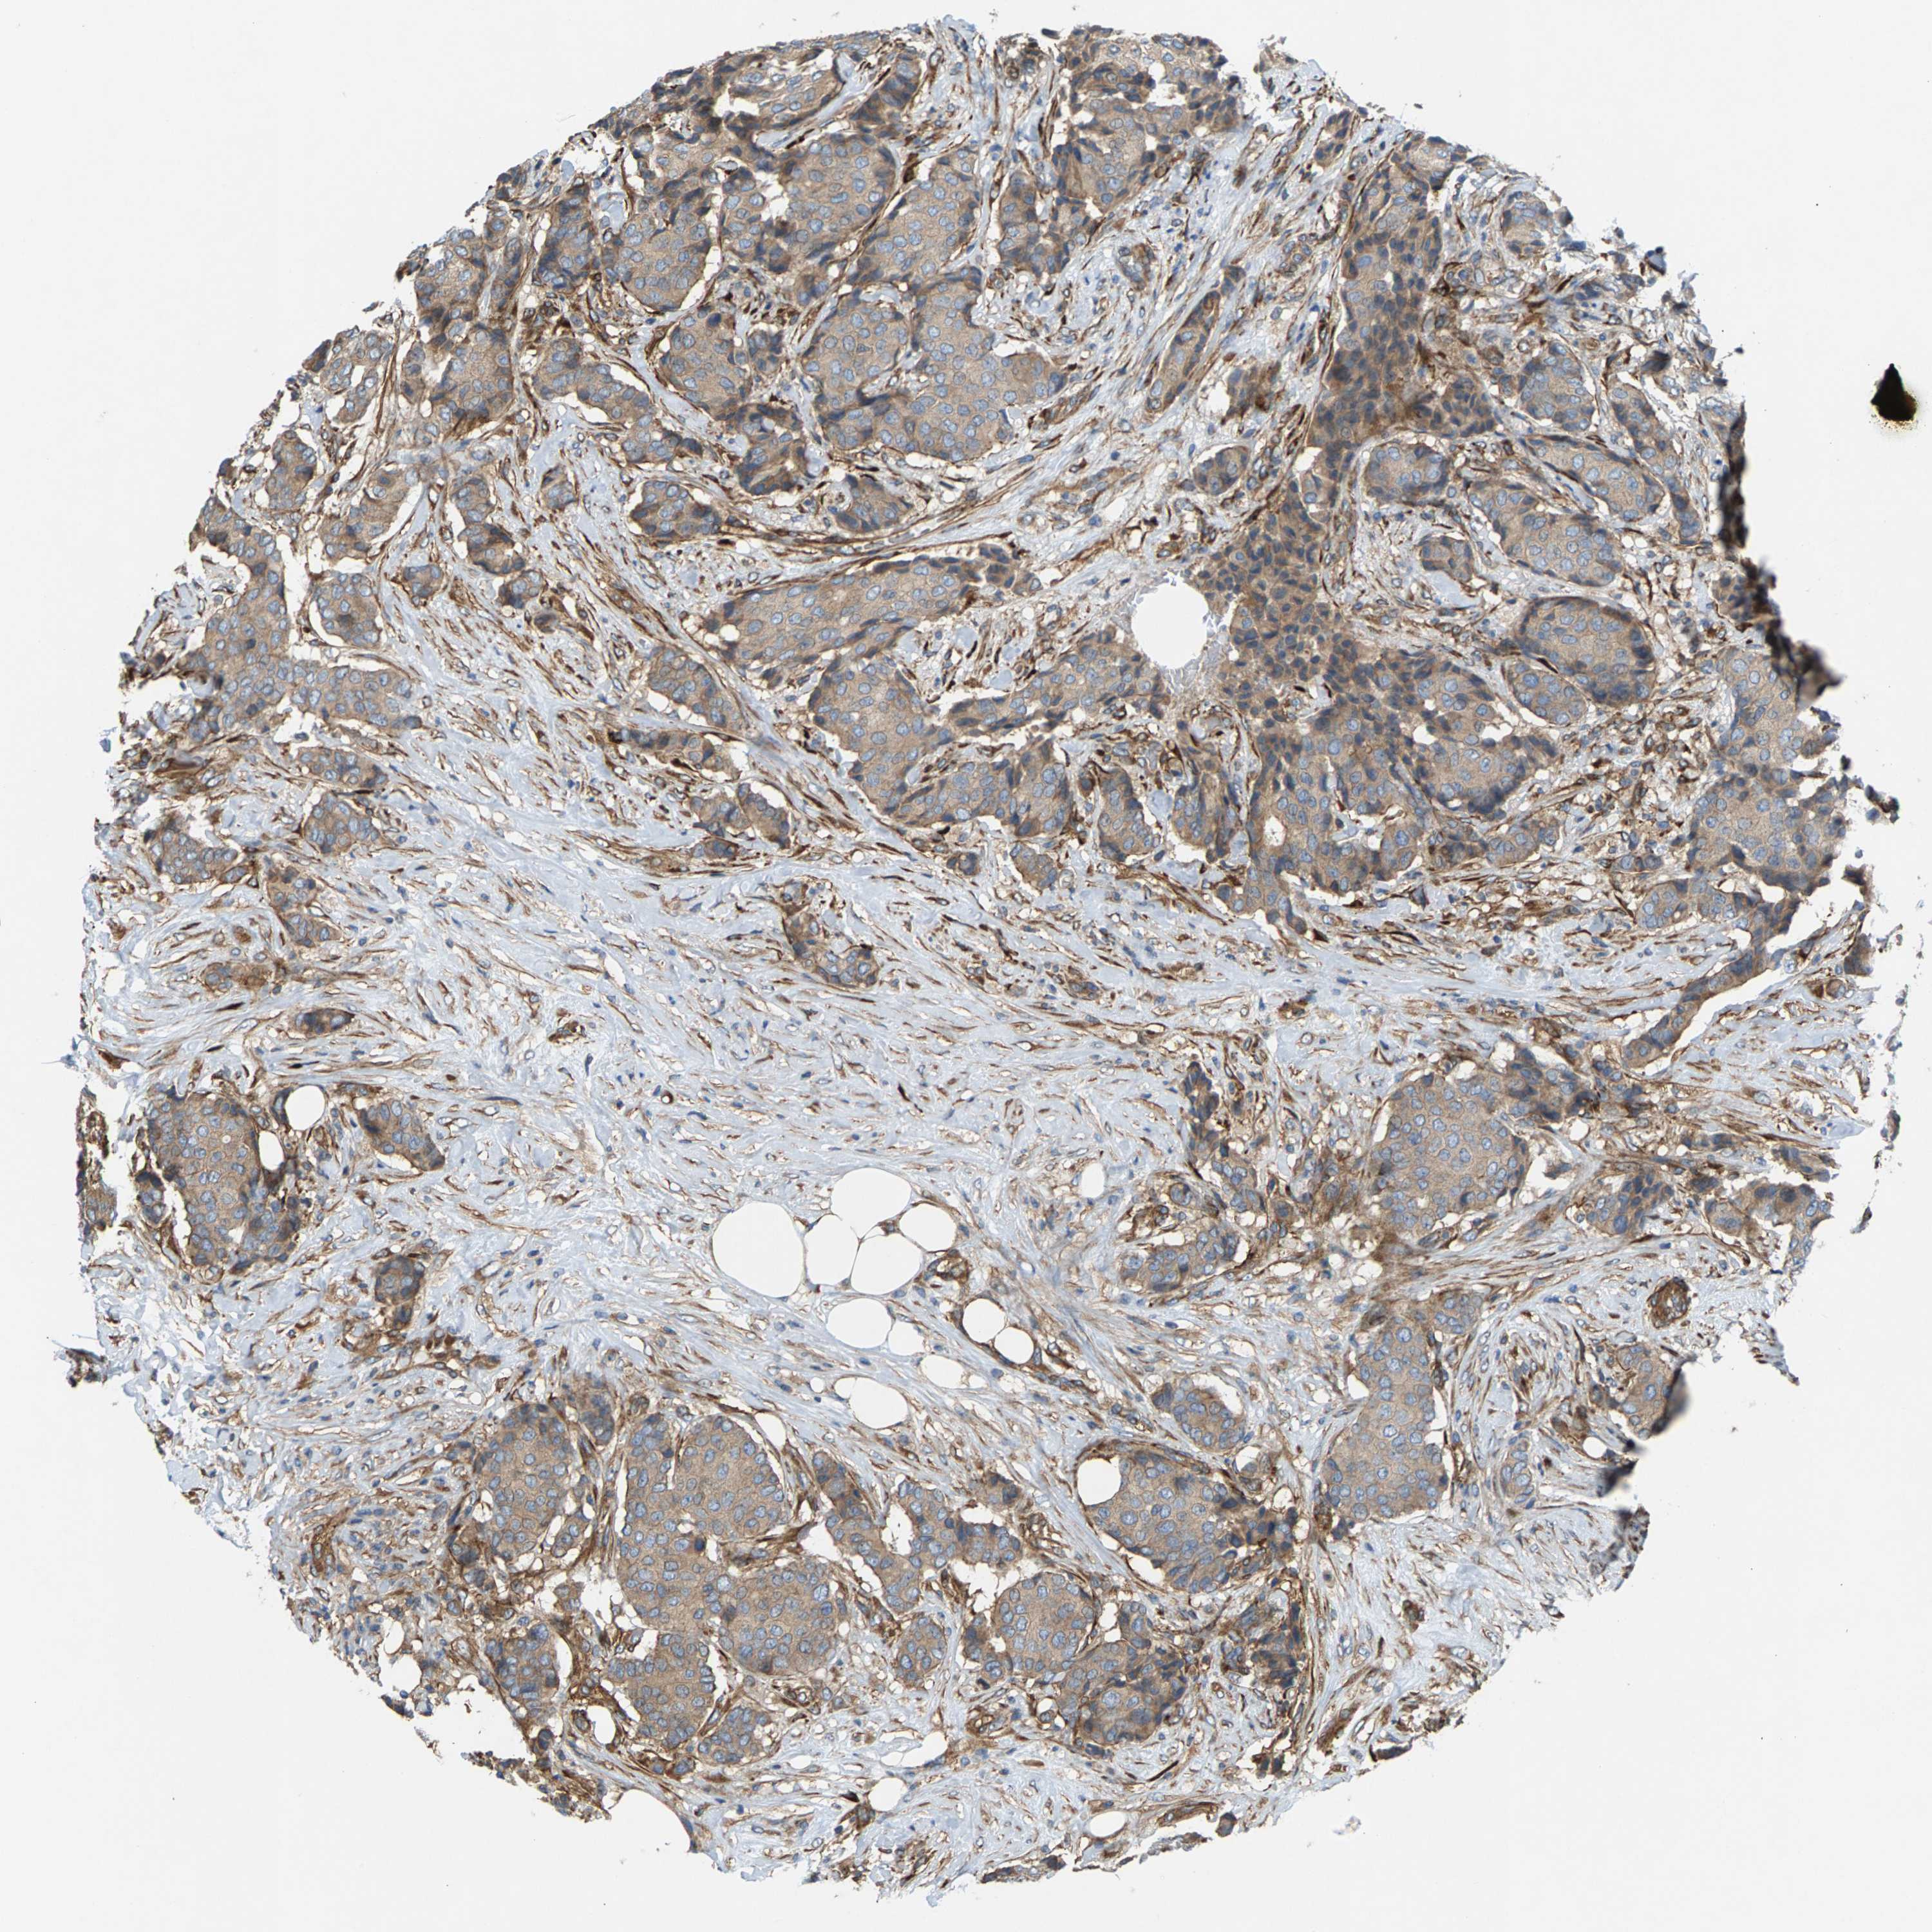

CANCER BREAST CANCER Show tissue menu

BRCA TCGA BRCA VALIDATION PROTEIN EXPRESSION